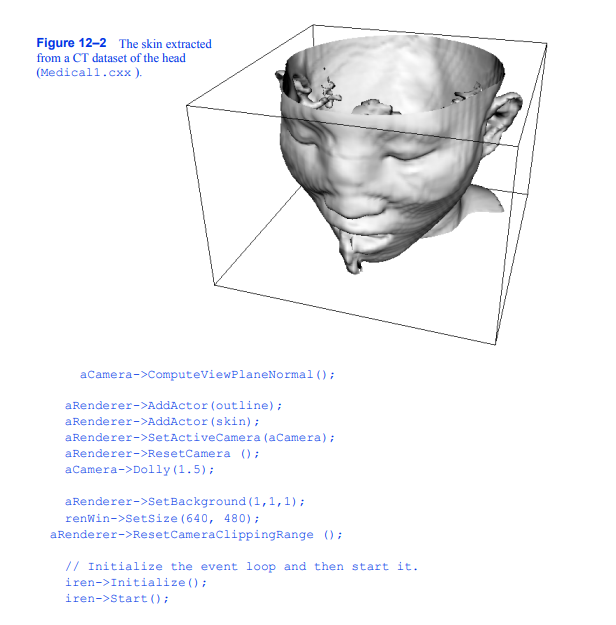

为了提供等值面的上下文,在数据周围创建一个轮廓。初始视图设置在像素大小的窗口中。由于移动相机命令移动到数据,剪辑平面重置,以确保等值面是完全可见的。图12 - 2显示了患者的皮肤图像。

我们可以通过多种方式改进这种可视化。首先,我们可以为皮肤选择更合适的颜色(和其他表面属性)。我们使用vtkProperty方法SetDiffuseColor()将皮肤颜色设置为肉色。我们还在皮肤表面添加了一个镜面组件。接下来,我们可以添加与各种解剖特征相对应的额外等值面。这里我们选择通过添加额外的管道段来提取骨表面。它由筛选器vtkMarchingCubes、vtkPolyDataMapper和vtkActor组成,就像我们对皮肤所做的一样。最后,为了提高系统的渲染性能,我们从输出中创建三角形条

轮廓的过程。这需要添加vtkStripper。图12 - 3显示了生成的图像,下面是该管道的c++代码。